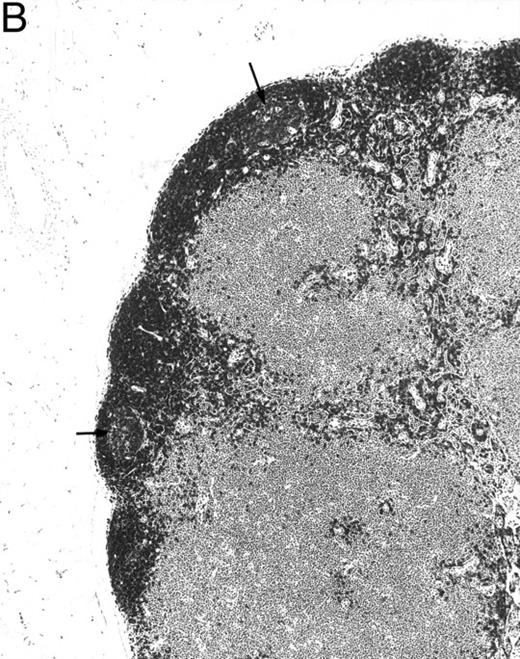

Histologic alterations occur in hematopoietic tissues of IFN-γ transgenic mice.Focal granulomatous lesions were seen in the bone marrow of many of the transgenic mice (Fig 4A) but not in control mice. These lesions were found to contain primarily Mac-2+ mononuclear cells (data not shown). In addition, the marrow cavities of IFN-γ transgenic mice contained residual degenerated cartilaginous masses in the metadiaphyseal (young) or diaphyseal (adult) parts primarily in long bones and ribs (Fig 4B). Moribund transgenic mice often had generalized or local secondary bacterial infectious lesions, including pyelonephritis, meningoencephalitis, endocarditis, bone marrow necrosis, arthritis, and uterine granulomas. Bacteria and bacterial colonies were often seen within the lesions.

Bone marrow alterations in IFN-γ transgenic mice. (A) Tibial bone marrow of a 3-month-old transgenic mouse showing granulomatous lesions (arrows) stained with H&E. The focal lesions were composed of clusters of histiocytes/macrophages (original magnification × 300; Bouin's fixed and paraffin-embedded section). (B) A rib of an 8-month-old transgenic mouse showing a cartilaginous mass in the marrow cavity attached to the cortical bone. Chondrocytes in the mass are degenerative. The mass is covered with a thin osseous layer. (Original magnification × 75; H&E; Bouin's fixed and paraffin-embedded section.)